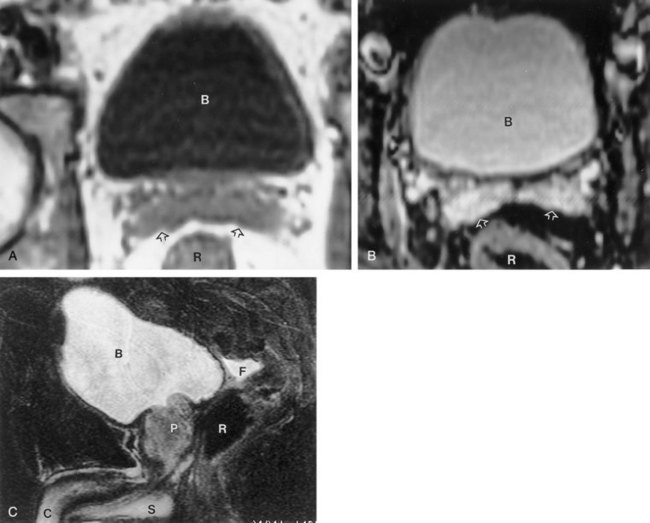

Some patients are not favorable candidates for renal ultrasonography. Obesity, intestinal gas, and physical deformity may be impediments to complete renal evaluation. Renal ultrasonography has poor sensitivity for renal masses less than 2 cm (Warshauer et al, 1988). There is a lack of specificity for renal tumor type except for angiomyolipoma. Angiomyolipoma has characteristics that are distinctive on ultrasonography (highly echoic), but some small renal cell carcinomas have been shown to be indistinguishable from angiomyolipoma by ultrasound criteria (Yamashita et al, 1992; Forman et al, 1993).

Transabdominal pelvic ultrasonography is a tremendously versatile tool for the urologist. It is a noninvasive method for evaluating the lower urinary tract and prostate in men and the bladder in women. A curved array transducer of 3.5 to 5 MHz is most commonly employed to perform transabdominal ultrasonography. In pediatric patients a higher-frequency transducer may be used. In cases where only a residual urine or bladder volume is to be determined, an automated bladder scanner is often employed.

Bladder ultrasonography is most commonly performed with the patient supine and the sonographer on the patient’s right side. The scan should be performed in a warm room, and the patient draped to provide for comfort and privacy. If necessary, a roll may be placed beneath the patient’s hips. Scanning technique depends on the circumstances and the reason for the examination but in general should be performed with a moderately filled bladder. The bladder should be scanned in a sagittal and transverse manner angling the probe into the pelvis so that the bladder can be visualized beneath the pubic bone. Although the prostate cannot be imaged with the same resolution achieved during transrectal scanning, the size and morphology of the prostate can be demonstrated. Although transabdominal scanning is the most common means of evaluating the bladder, the bladder may also be assessed via a transvaginal and transrectal approach. These approaches are useful in patients who are obese or who are not suitable candidates for transabdominal scanning.

Transabdominal pelvic ultrasonography should include evaluation of the lumen of the bladder, as well as bladder wall configuration and thickness. The presence of specific lesions such as stones or tumors should be documented. The structures immediately surrounding the bladder may also be evaluated including the distal ureters, the prostate in men, and the uterus and ovaries in women (Fig. 4–34). The emergence of urine from the ureteral orifices (ureteral jets) can be demonstrated. The clinical value of demonstrating ureteral jets has been questioned. Up to 10 minutes of continuous observation may be required to verify the absence of a ureteral jet (Fig. 4–35) (Delair and Kurzrock, 2006).